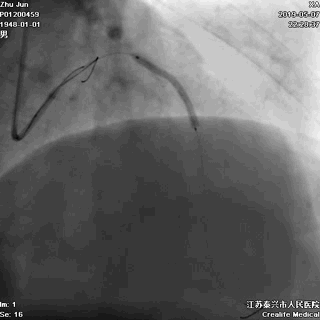

导丝分别进回旋支和前降支

LAD和LCX,任一根血管都不能丢!这一步的价值,就相当于是构筑生命线。

前降支至左主干行PTCA

前降支植入第一枚STENT

前降支-左主干STENT定位和植入